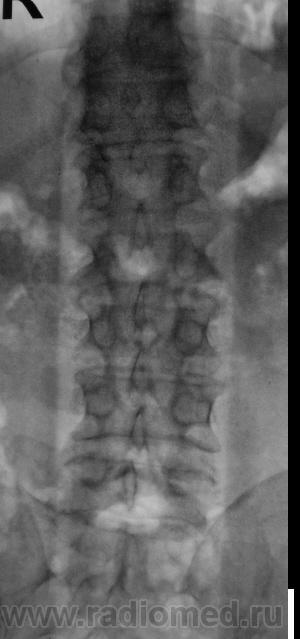

Пол пациента: Мужской пол Тип патологии: Другое Область исследования: Скелетно-мышечная система Методы исследования: Rg Пациент направлен на рентгенографию поясничного отдела позвоночника. https://radiomed.ru/sites/default/files/styles/case_slider_image/public/user/12/2.pb100007a.jpg?itok=U7NupSFv https://radiomed.ru/sites/default/files/styles/case_slider_image/public/user/12/3.pb100008.jpg?itok=uQAcfJjo https://radiomed.ru/sites/default/files/styles/case_slider_image/public/user/12/4.pb100008a.jpg?itok=HrnStjvs ID:8713 Thu, 11/11/2010 - 17:40 #1 Helios Offline Last seen: 8 months 4 days ago Joined: 06.08.2010 - 15:16 Posts: 4417 Остеохондроз, деформирующий спондилез и , кажется, spina bifida крестца. Thu, 11/11/2010 - 21:47 #2 Глазков Игорь А... Offline Last seen: 9 months 4 weeks ago Joined: 19.12.2008 - 20:41 Posts: 1597 spina bifida крестца. Узелки Шморля в 2,3,4 позвонках. Остеохондроз поясничного отдела позвоночника. Прийди к Себе Wed, 17/11/2010 - 17:19 #3 Сан Саныч1 Offline Last seen: 12 months 1 day ago Joined: 07.06.2010 - 21:17 Posts: 2114 И спондилолиз Л5 слева. Хочешь сделать что-то нормально - сделай это сам!

Остеохондроз, деформирующий спондилез и , кажется, spina bifida крестца.

spina bifida крестца. Узелки Шморля в 2,3,4 позвонках. Остеохондроз поясничного отдела позвоночника.

И спондилолиз Л5 слева.